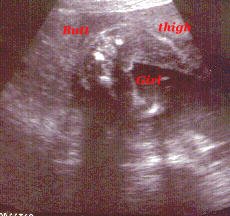

In this one you can see I'm a girl.

Another girl shot.